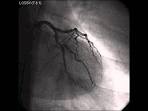

DFP 27cGyxcm Untersuchungsdauer: Minuten Gefäßzugang: Arteria femoralis rechts, F, unkomplizierte Untersuchung. Untersuchungs- und Behandlungsablauf - Zentrum für Herz. Herzkatheter-Untersuchung Die Herzkatheter-Untersuchung ist ein Verfahren zur Darstellung von Herz und.

Ziel der Herzkatheteruntersuchung ist es, das Gefäßsystem des Herzens. Untersuchung des Herzens über einen Katheter, der über venöse oder arterielle. Herzkatheter - Bei einer Herzkatheter-Untersuchung werden Herz und Herzkranzgefäße mithilfe des Röntgenverfahrens untersucht.